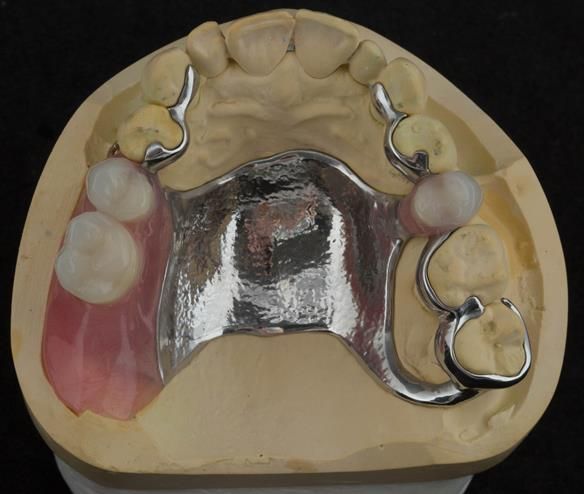

This newsletter describes in step by step detail Angela's transition through immediate partial dentures to crown supported definitive metal based dentures.

The clinical situation and treatment process is shown in detail below with photographs. I (Finlay Sutton) provided the clinical work and Rowan Garstang provided the technical work.